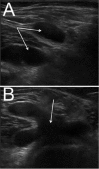

Context: Popliteal synovial cysts, also known as Baker's cysts, are commonly found in association with intra-articular knee disorders, such as osteoarthritis and meniscus tears. Histologically, the cyst walls resemble synovial tissue with fibrosis evident, and there may be chronic nonspecific inflammation present. Osteocartilaginous loose bodies may also be found within the cyst, even if they are not seen in the knee joint. Baker's cysts can be a source of posterior knee pain that persists despite surgical treatment of the intra-articular lesion, and they are routinely discovered on magnetic resonance imaging scans of the symptomatic knee. Symptoms related to a popliteal cyst origin are infrequent and may be related to size.